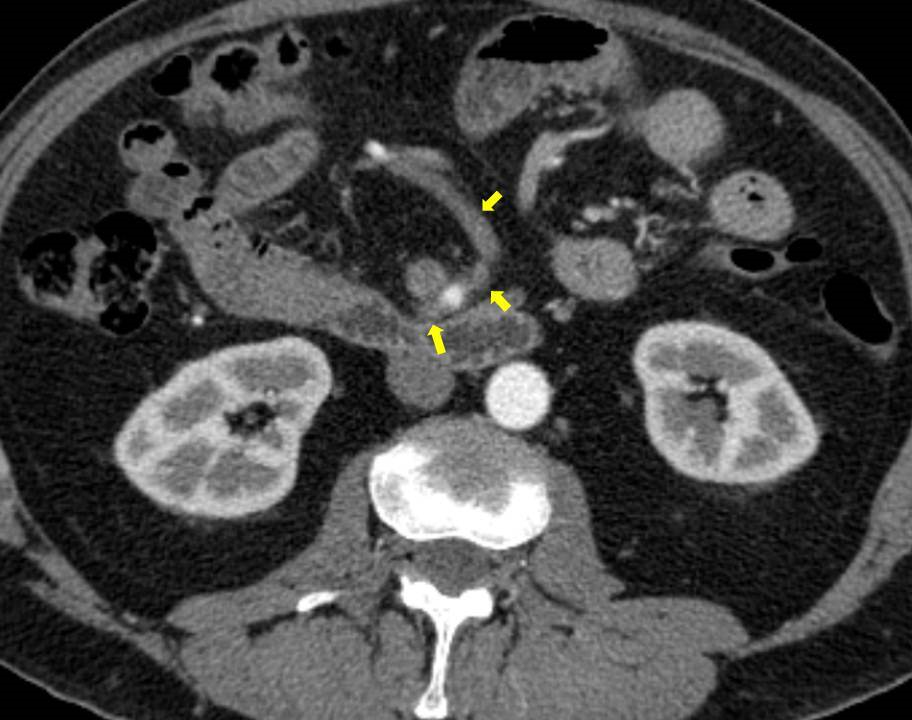

Acute abdominal pain is one of the most common conditions encountered in the emergency department. The differential diagnosis of acute abdominal pain is extensive and identifying the underlying etiology can be challenging. We report a case of acute transient ischemic jejunitis due to symptomatic isolated superior mesenteric artery dissection in a patient with no cardiovascular risk factors or autoimmune diseases. Symptomatic isolated superior mesenteric artery dissection is a rare cause of acute abdominal pain usually treated in the surgical department. The patient had criteria for conservative treatment and rapidly recovered. We highlight a rare condition which should be taken into account for the differential diagnosis of acute abdominal pain.